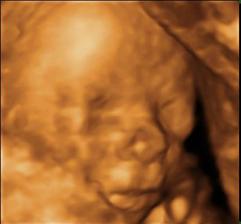

Nase troj rocne snazenie 🙂